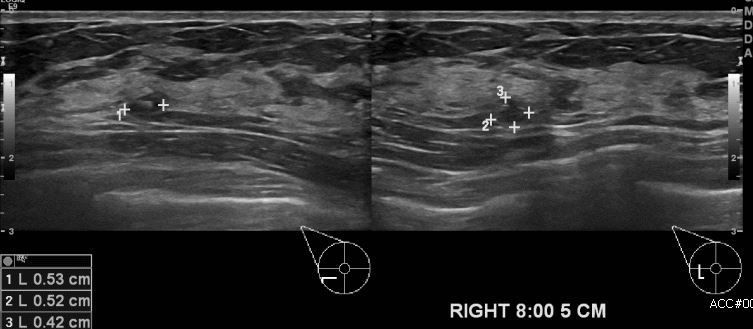

양측 만져지는 멍울로 내원하신 30대 여성분으로 본원 유방초음파 시행후  우측 8시

방향에서 8cm 떨어진 거리의 멍울 조직검사 시행하여   우측 유관암 진단 되었습니다.